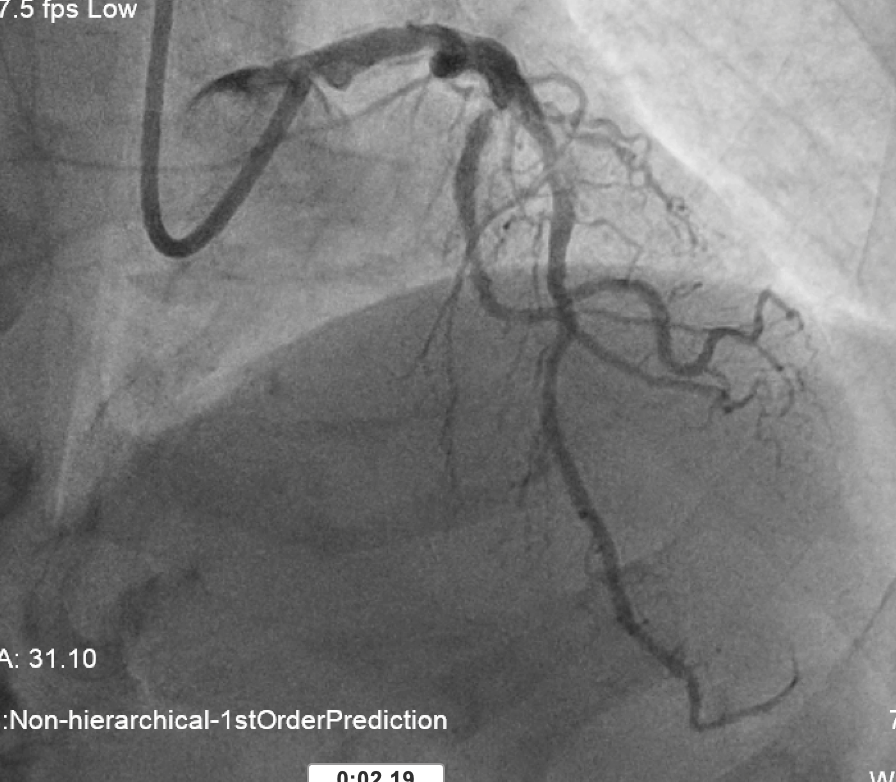

•Very calcified vessels •LM: diffuse disease •LAD: pLAD and mLAD severe stenosis •LCx: mLCx critical stenosis •RCA: dominant, mRCA critical lesion

L system coro 2.mov

L system coro 1.mov